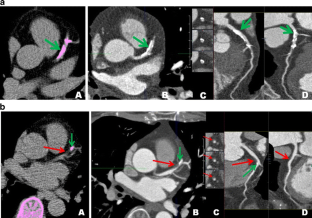

Fig. 1

Fig. 2

Fig. 3